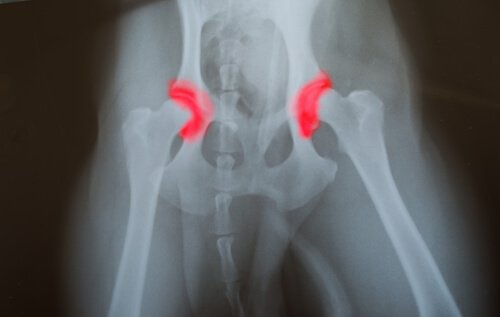

- Hip dysplasia

Compared with large dogs that have an unbalanced diet, those that ate a balanced one had fewer diseases associated with overgrowth. Hip dysplasia was one of the most common diseases in large, overfed dogs.